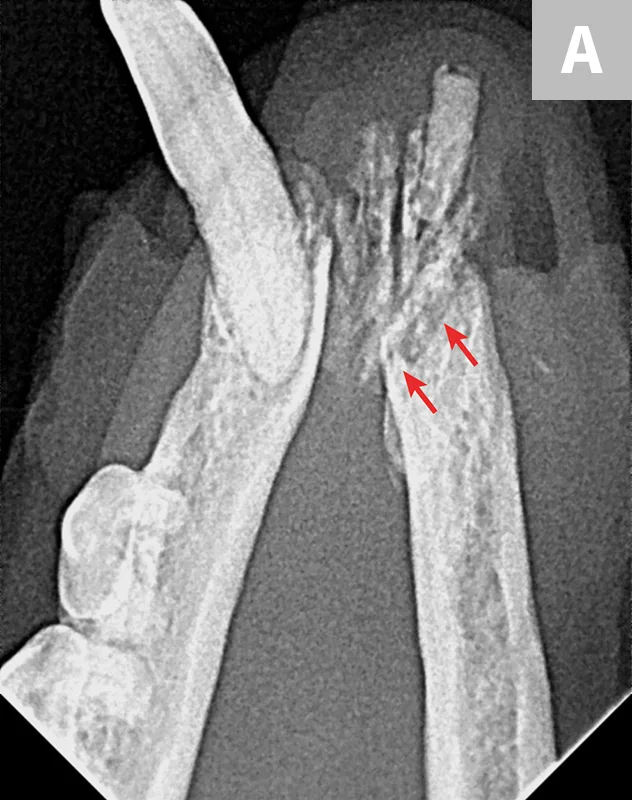

Dental X-ray with arrows pointing to root fractures of the 4th maxillary premolar in a dog.

FIGURE 1

Fracture of the mesiobuccal and distal roots (arrows) during extraction of the left maxillary 4th premolar tooth in a dog

1. Root Breakage

Mucoperiosteal flaps should be developed for most extractions to allow for appropriate exposure for alveolar bone removal, which allows for better visualization and subsequent tooth root elevation.2-4 As a general rule, buccal alveolar bone should be removed before elevation is attempted to expose, at minimum, approximately half of the root.5 A small bur can be used to create a mesial and distal space to allow for placement of a dental elevator. Tooth root elevation is a slow process that fatigues the periodontal ligament; if abrupt force is applied before the periodontal ligament is fatigued or severed, the root often fractures (Figure 1). Adequately exposing soft and hard tissues at the beginning of the procedure can save time and allow for successful root removal; however, even if careful and appropriate techniques are used, roots may still break during extraction (eg, due to tooth resorption or ankylosis of the root to the alveolus). If a root breaks, additional removal of alveolar bone is often necessary to retrieve the remaining root fragment.